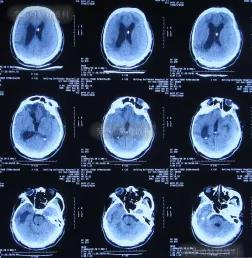

入院治疗88天即2020年4月15日出院,出院时:病情好转为,意识变清,肢体能遵嘱活动,变得能坐轮椅活动,比入院时体重明显增加(图-15);出院时头颅CT示未见异常(图-16)。

图-15:2020年4月15日出院时

图-16:头颅CT出院时